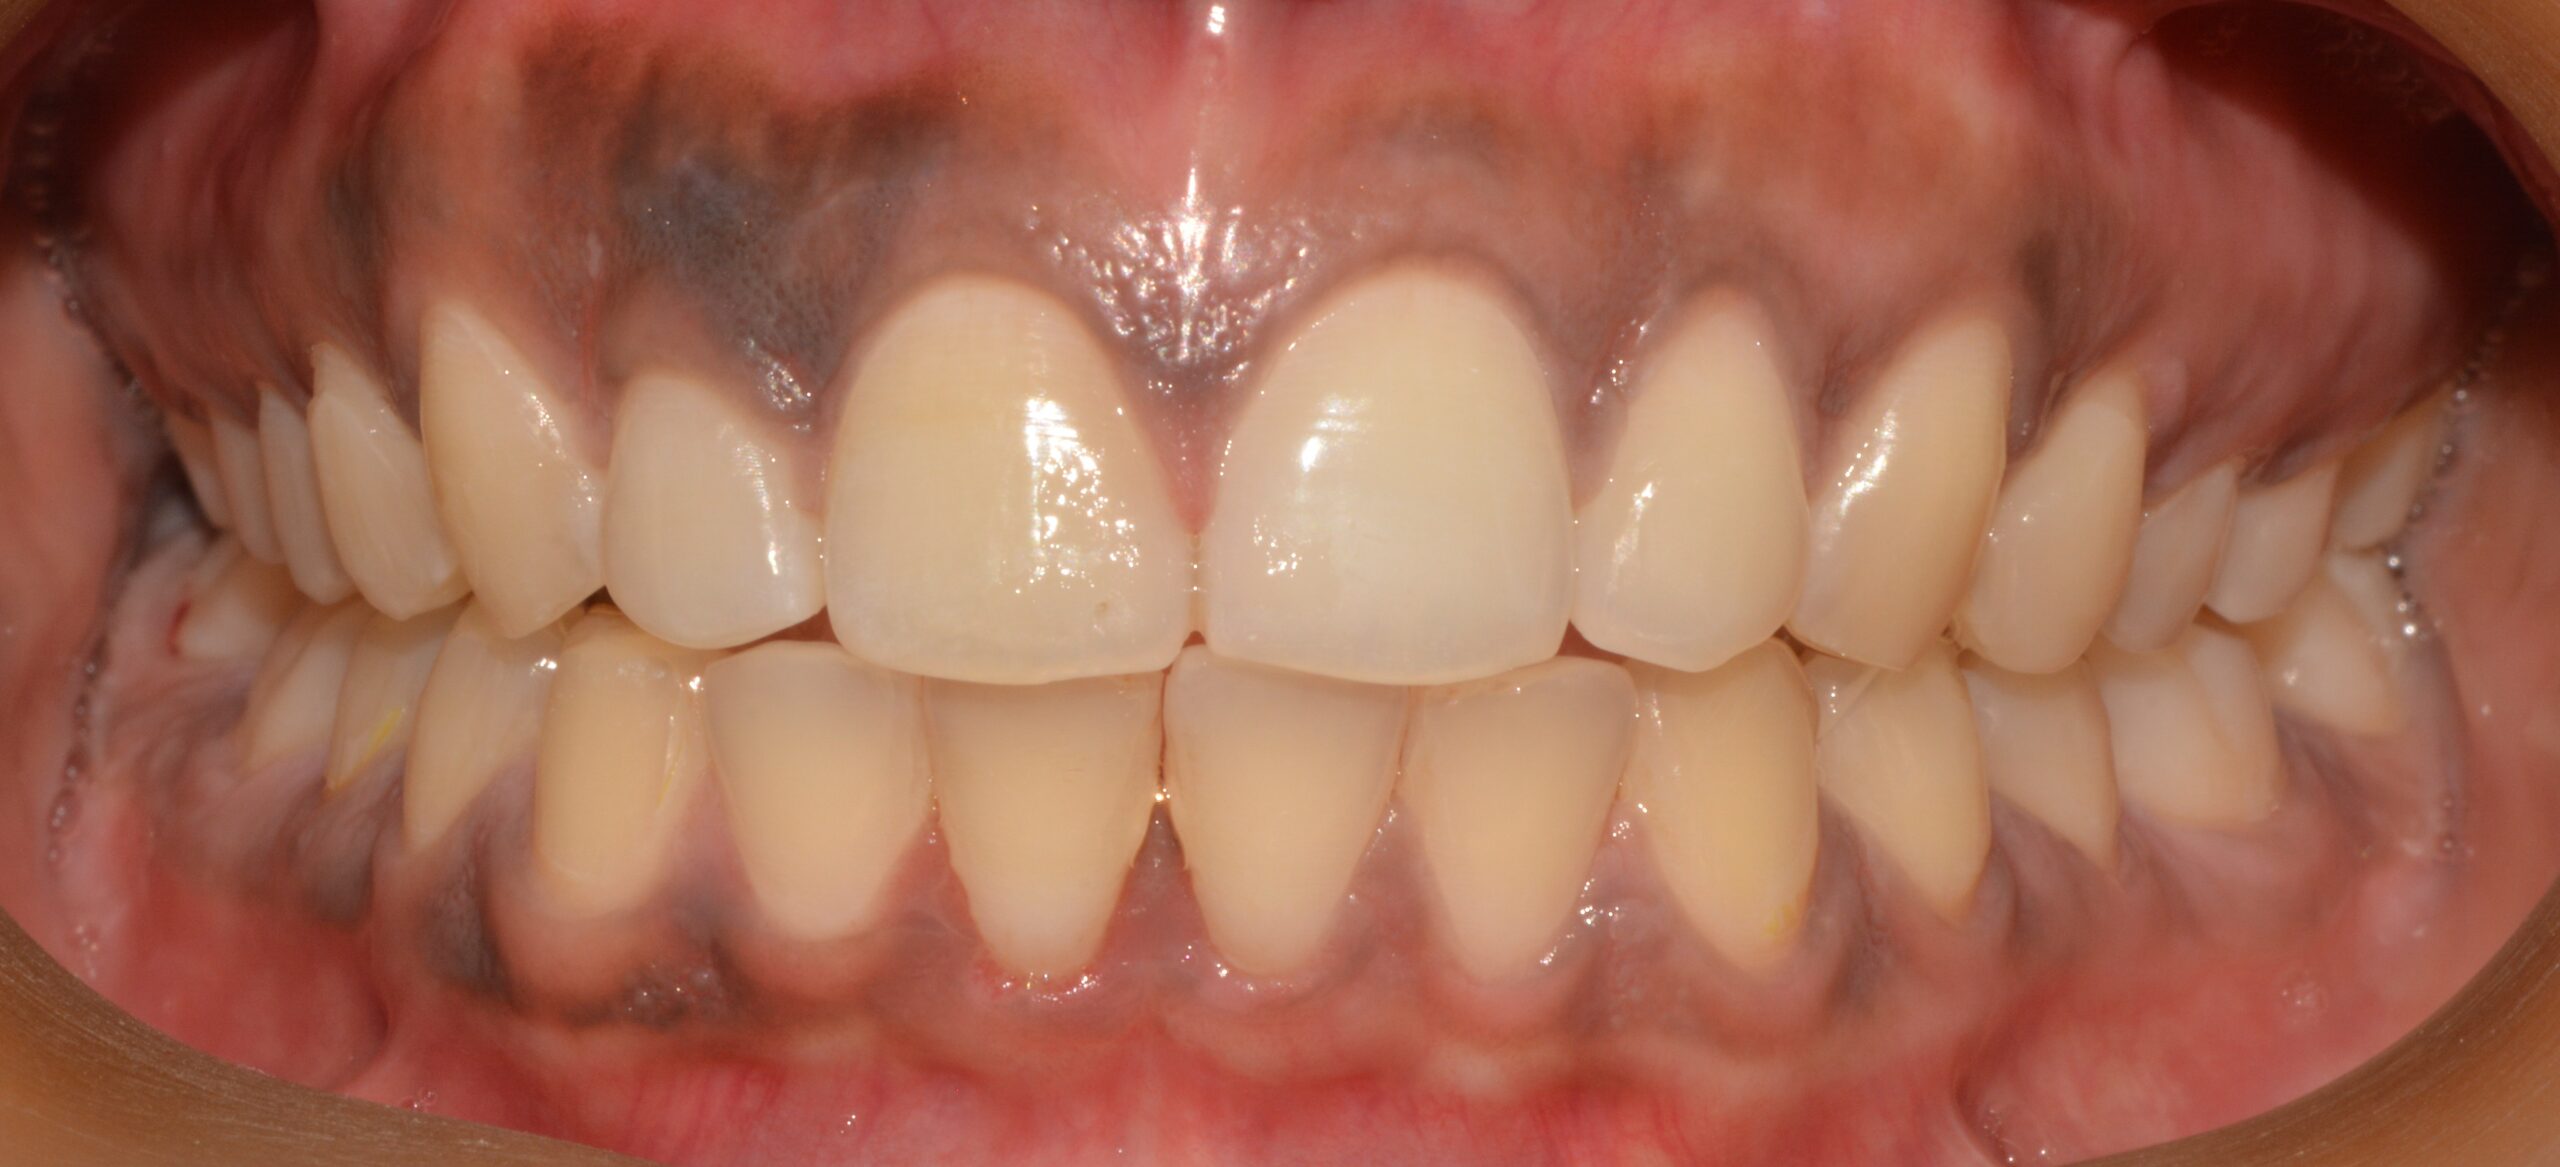

The patient was treated with aligner therapy using Invisalign aligners, which applied light forces to close the gaps. This treatment also helped the loose lower front teeth become stable over time, preventing the need for tooth removal and future implants.

The total treatment duration was between 18 to 20 months.

After